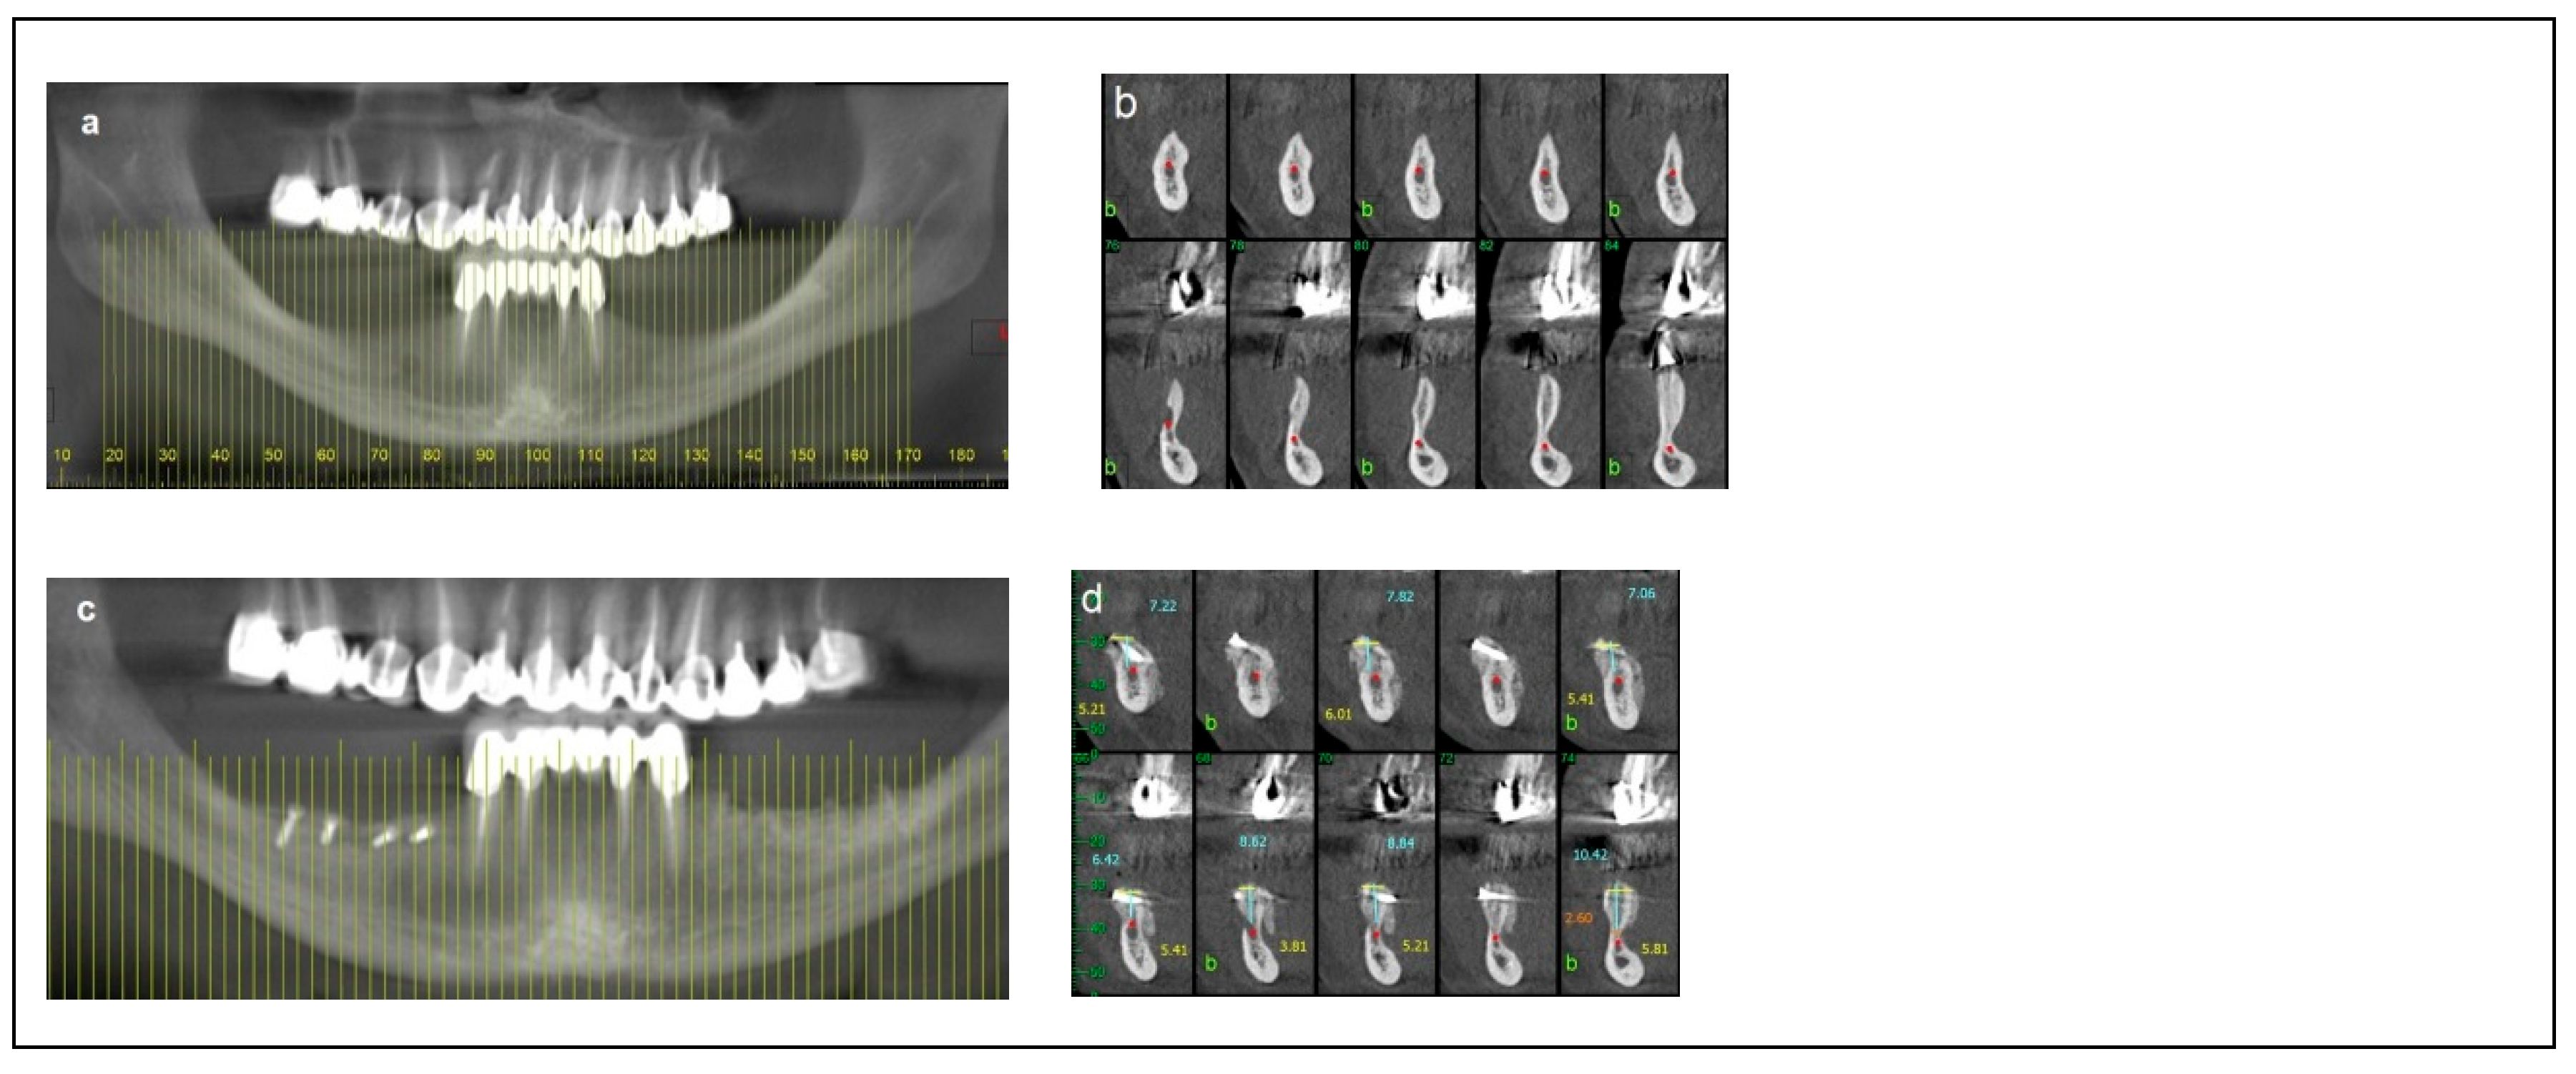

2.1. Category 1

2.2. Category 2